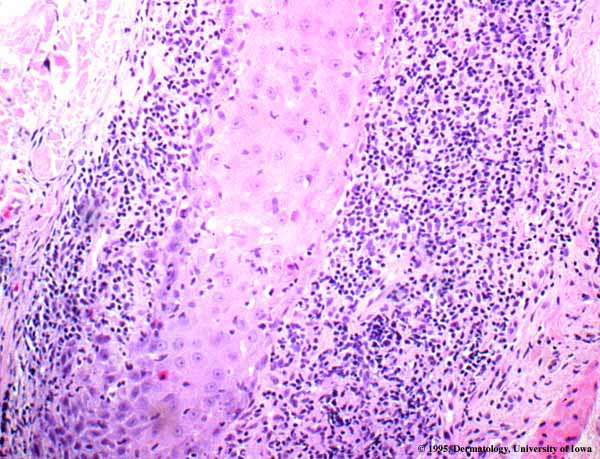

Squamotization in Lichen Planopilaris = التشوك في الحزاز المنبسط الجرابي